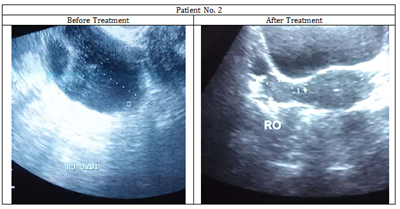

11/3/2014 Bulky right ovary  and presence of  right ovarian cyst [47mmX35mm]

USG showed no abnormality.

(Figure 3& 4)

Figure 3 Images of Ultra-sonography of the patient No. 2 showing removal of the cyst from right ovary.

Figure 4 Ultra-sonographic reports of the patient No. 2 showing removal of the cyst from right ovary..

From analysis of the change in ameliorating symptoms or recurrence of unwanted symptoms, the suitable potencies were prescribed; initially all three patients received the 30C potency and advised to come after one month. In all the patients, amelioration of symptoms like irregularity of menstruation, reduction in intensity of pain was noticed after administration of the 30C potency to a varying degree. Whenever there was a recurrence of symptoms after a period of steady amelioration, the next higher potency was chosen. And when all the symptoms were totally gone gradually, the final USG was advised for checking whether the cysts had also been removed. In all the patients, USG revealed presence of the cysts before drug administration, but finally in all the cases there was no more any trace of the cysts.